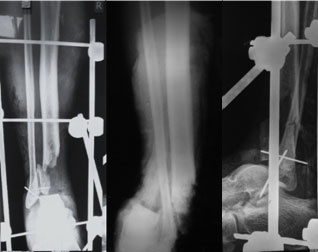

The xrays after 1 week of debridement and VAC dressing. The xray on the left side is as seen from the front (AP view) and the one on the right is as seen from the side (Lateral view) |